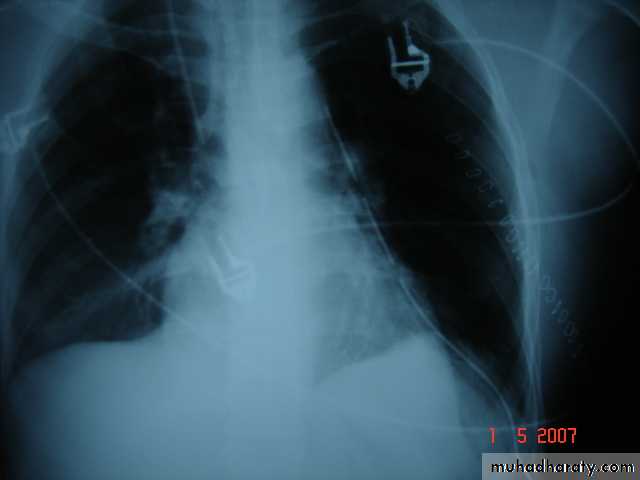

• Tube Thoracostomy Tube thoracostomy or Chest Tube or ICD(Intercostal drain) Is a flexible hollow plastic tube that is inserted through the chest wall into the pleural space and connected to a bedside drainage container

• Indications:-

• 1-Pnemothorax

• 2-Pleural Effusion This effusion may be A-Empyema

• 2-Hemothorax Traumatic or Malignant Effusion

• 3-Hydro thorax 4-Chylothorax 5-Thoracic Operation (Tube Thoracostomy without trocar ) .On the lung or Mediastinum Or The esophagus 6-Postoperative (Collection or Infected space ).7-malignant Effusion drainage and giving medication through it.

• Chest radiograph to be taken to check the location of the drain